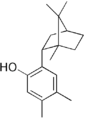

- 220px-Magnesium pyridoxal 5-phosphate glutamate.png سلام المجذوب

05:23، 10 سبتمبر 2012

220 × 158؛ 6 كيلوبايت